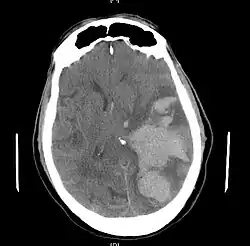

MRI showing damage due to herniation. This patient was left with residual disabilities including those involving movement and speech.[16]

Treatment involves removal of the etiologic mass and decompressive craniectomy. Brain herniation can cause severe disability or death. In fact, when herniation is visible on a CT scan, the prognosis for a meaningful recovery of neurological function is poor.[2] The patient may become paralyzed on the same side as the lesion causing the pressure, or damage to parts of the brain caused by herniation may cause paralysis on the side opposite the lesion.[11] Damage to the midbrain, which contains the reticular activating network which regulates consciousness, will result in coma.[11] Damage to the cardio-respiratory centers in the medulla oblongata will cause respiratory arrest and (secondarily) cardiac arrest.[11] Investigation is underway regarding the use of neuroprotective agents during the prolonged post-traumatic period of brain hypersensitivity associated with the syndrome.[17]